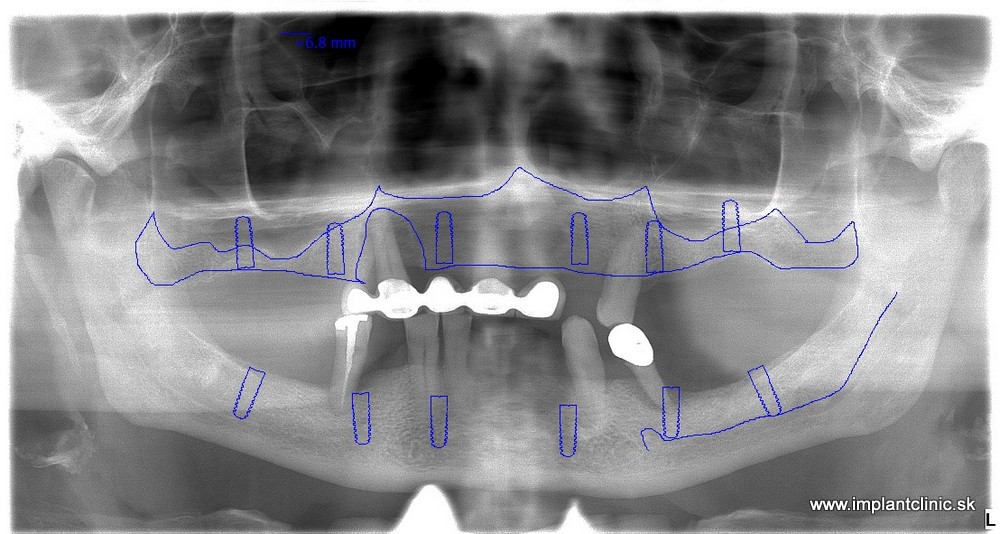

Michal sa objednal na konzultáciu v Implantclinic. Náš hlavný implantológ MUDr. Salka navrhol komplexnú rekonštrukciu chrupu hornej čeľusti a sánky. Konkrétne sa jednalo o zavedenie 7 zubných implantátov v hornej čeľusti a 6 zubných implantátov v sánke.

RTG snímka pred a po ošetrení: